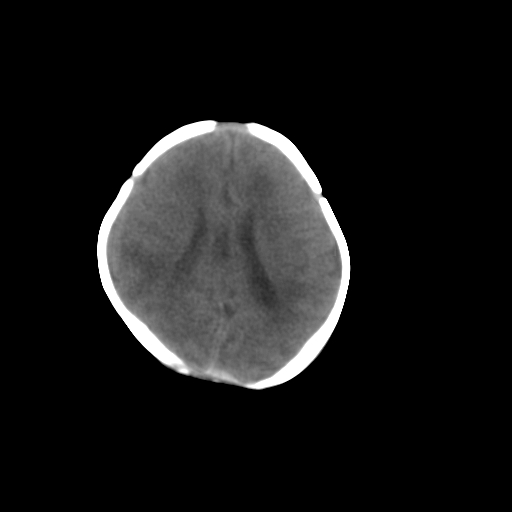

标题: PED1017:女,3天,足月顺产,出生后精神反应弱2小时。

女,3天,足月顺产,出生后精神反应弱2小时。

蛛网膜囊肿,胼胝体发育不良

1)考虑hie。2)枕部颅骨内板下方类似囊状脑脊液样低密度影,鉴别于蛛网膜囊肿与巨大枕大池之间。

大枕大池,hie.